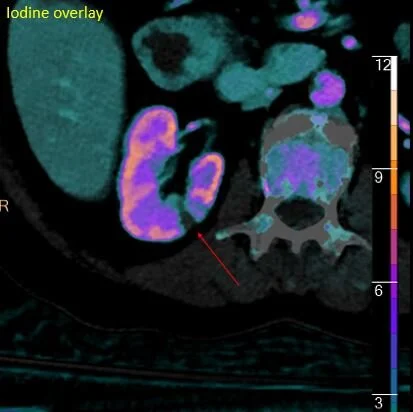

Iodine overlay shows there are actually 2 infarcts present (red arrows).